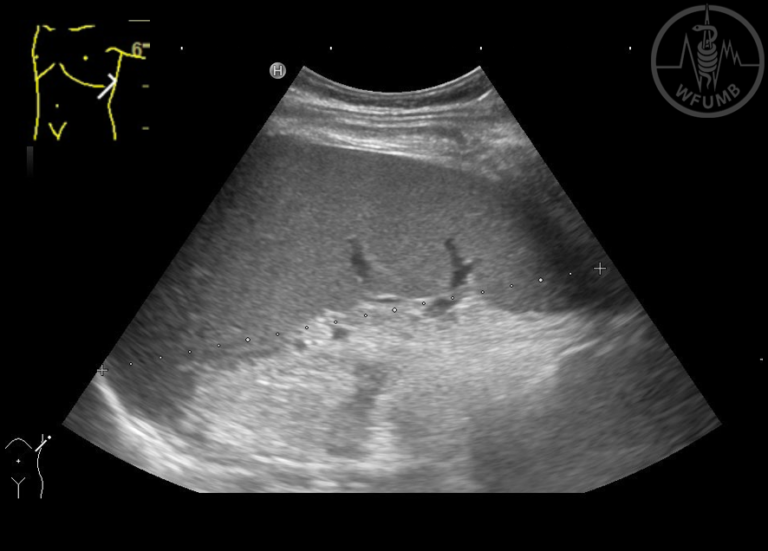

From wfumb.info

Spleen and Lymph Nodes Chapter 16 Media Library WFUMB How Long Is Spleen Enlarged After Mono Even after symptoms go away, it may take a few additional weeks for the swelling in your spleen to go down, so you’re still at higher risk of rupturing it than usual. The incubation period refers to how long before your symptoms appear after being exposed to the virus. This might happen in a fall or from. Vigorous activity or. How Long Is Spleen Enlarged After Mono.